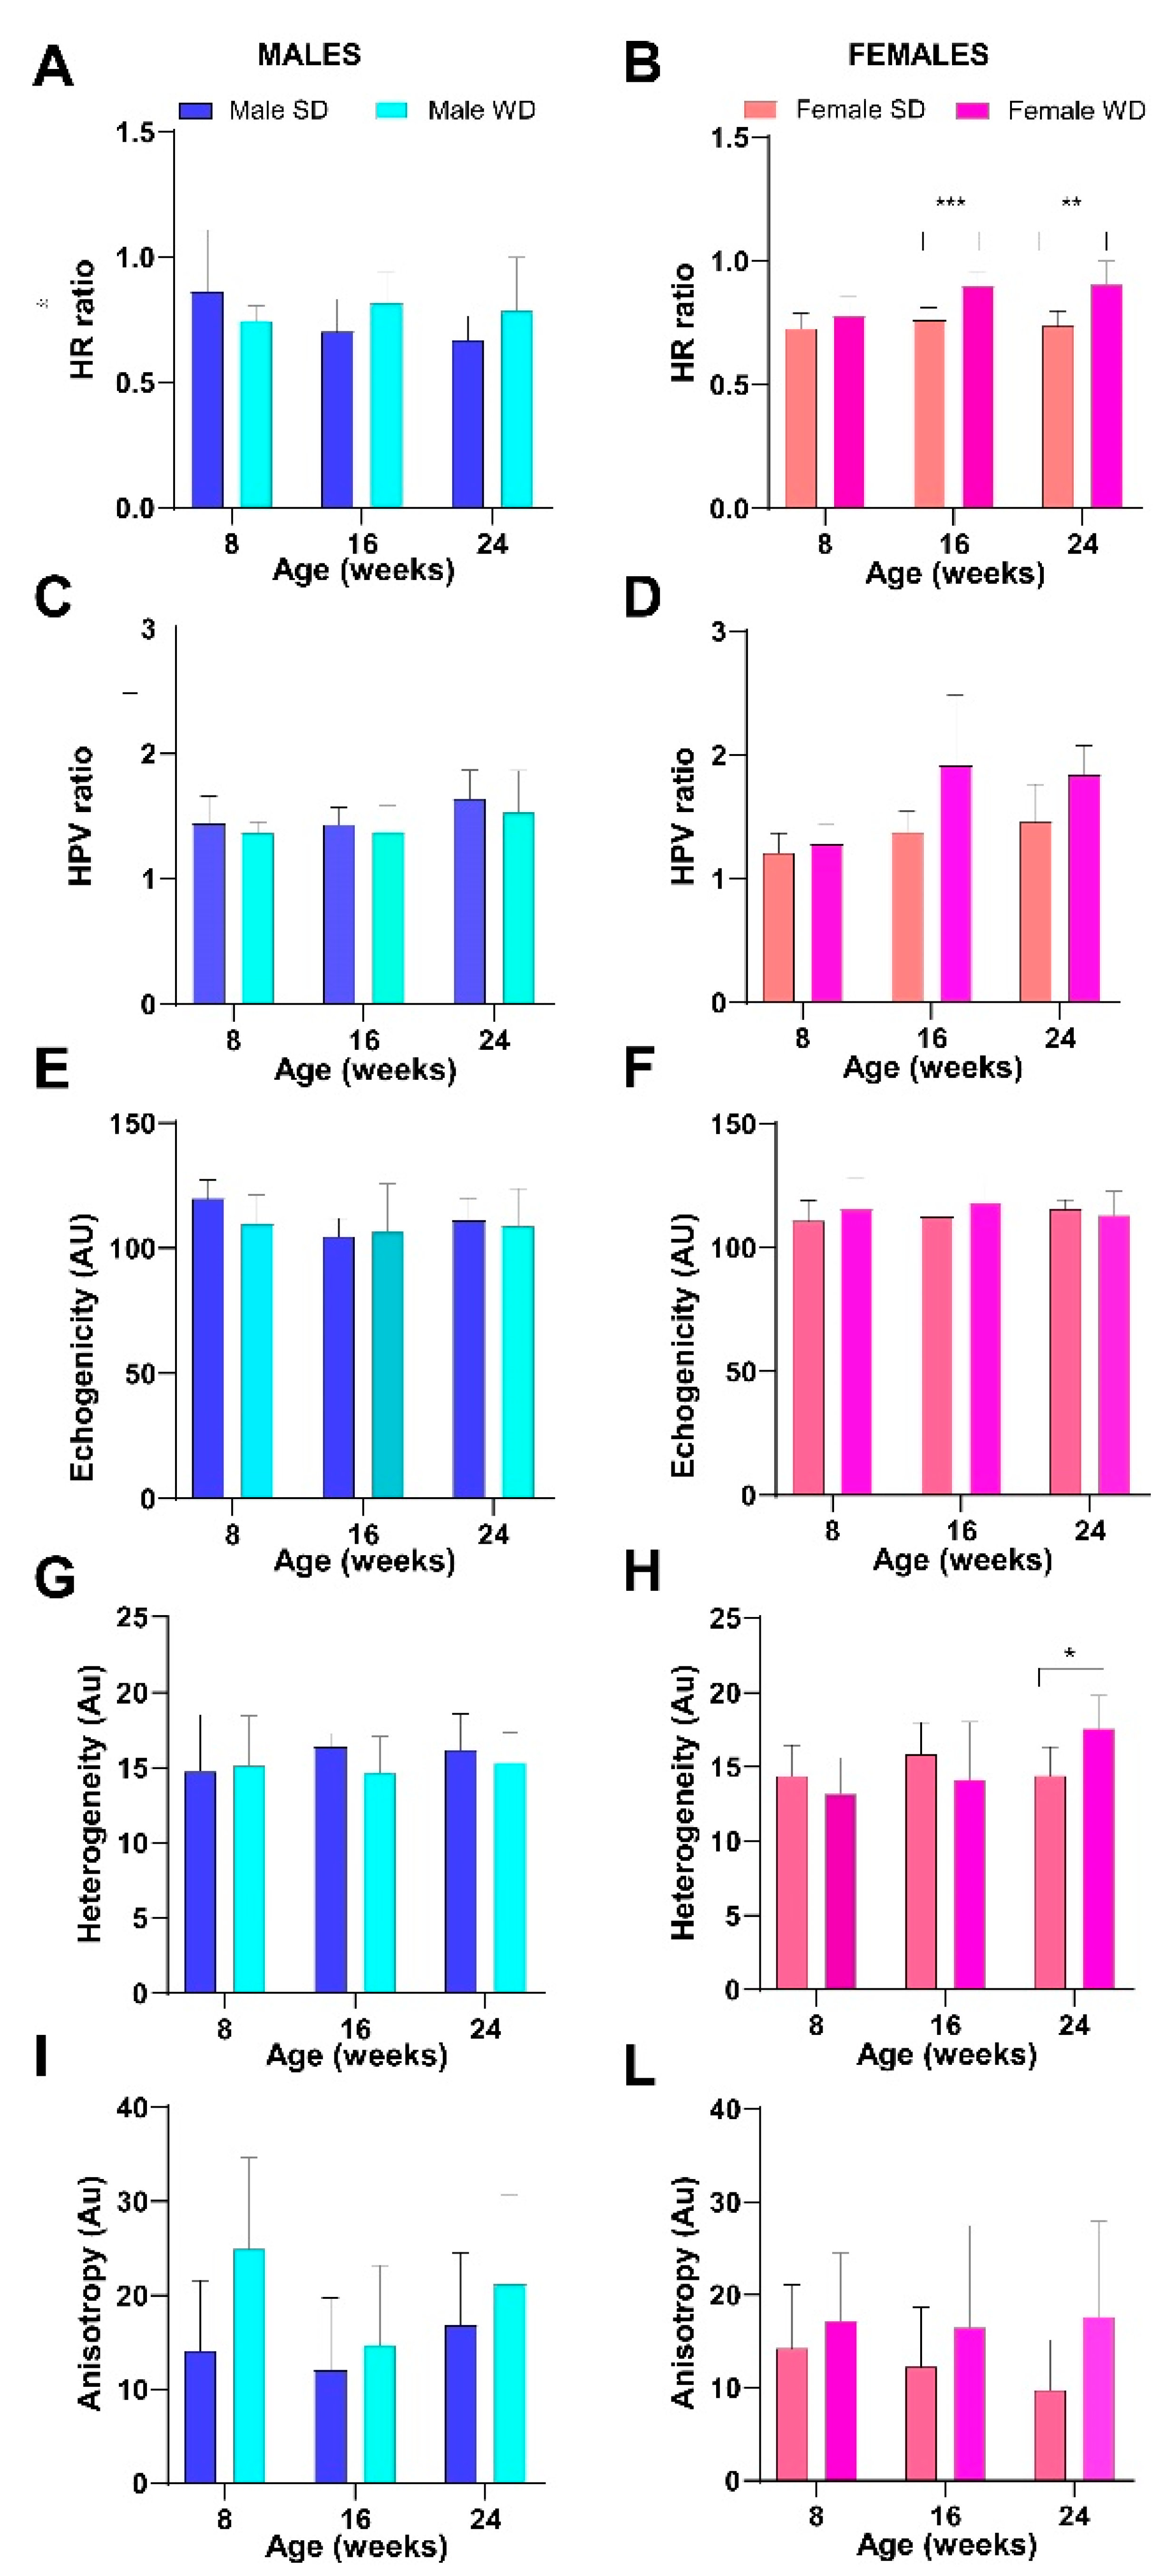

- Parametric analysis: Overall, normal hepatic parenchyma is less echogenic than the right renal cortex in rodents [7]. The hepatic echogenicity increases due to the presence of fatty infiltration and/or fibrosis, changing the relation between the liver and the right renal cortex [12].

- Hepatic-renal ratio (HR): A longitudinal view was acquired in order to have both the liver (caudate lobe) and the right kidney clearly visualized. Liver echogenicity was compared with that of the renal parenchyma, to normalize differences in the overall ultrasound gain value used for the acquisitions. A region of interest (ROI, (0.1 ± 0.02 mm2) was manually drawn and placed in the liver parenchyma, avoiding focal hypo- and hyperechogenicity. A second ROI was positioned in correspondence with a portion of the renal cortex devoid of large vessels along the focusing area of the image at the same distance from the probe to avoid distorting effects in ultrasonic wave patterns. HR values were obtained by dividing the mean grey level of the hepatic ROI for that obtained for the renal one (pixel intensity = average intensity/mm2, arbitrary units, a.u.) [9,44].

- Hepatic-portal vein ratio (HPV): Similarly, liver echogenicity was normalized to that corresponding to blood within the portal vein. Axial plane ultrasound images were acquired to visualize a portion of the portal vein in the center of the liver. One ROI (0.1 ± 0.02 mm2) was manually drawn and positioned within the lumen of the portal vein, while a second one was positioned in the liver parenchyma avoiding focal hypo- and hyperechogenicity, at the same depth and as close as possible to the center of the image, to maintain comparable ultrasound attenuation and avoid effects related to borderline echo distortion [9,44].

- Gray-level histogram analysis of echogenicity (GLH): Liver images at different scanning planes (left lateral lobe, longitudinal; caudate lobe, longitudinal; right median lobe, axial) were analyzed using a gray-level histogram to obtain the quantitative mean and standard deviation values of echogenicity of each spatial region. Anatomical landmarks (greater curvature of stomach; cranial pole of the right kidney; porta hepatis, at the level which aorta, portal vein, and caudal vena cava are visible in cross-section) were chosen to scan reproducible imaging planes. ROIs (1 ± 0.02 mm2) were manually drawn in the liver parenchyma, avoiding focal hypo- and hyperechogenicity and as close as possible to the center of the image. This approach includes more representative parts of the liver parenchyma and avoids distortion of image artifacts, with good intra-observer reproducibility [46]. Changes in brightness and variance of the liver parenchyma were reported as follows: mean echogenicity of different lobes; standard deviation of brightness within ROI encompassing right median lobe as measure of tissue heterogeneity; standard deviation of brightness among ROIs in all planes imaged as measures of anisotropy [46,47].

3.6. WD Causes Progressive Structural and Functional Changes in the Heart, Liver, and Kidney of C57Bl/6J Mice That Can Be Detected Early and Monitored In Vivo by HFUS